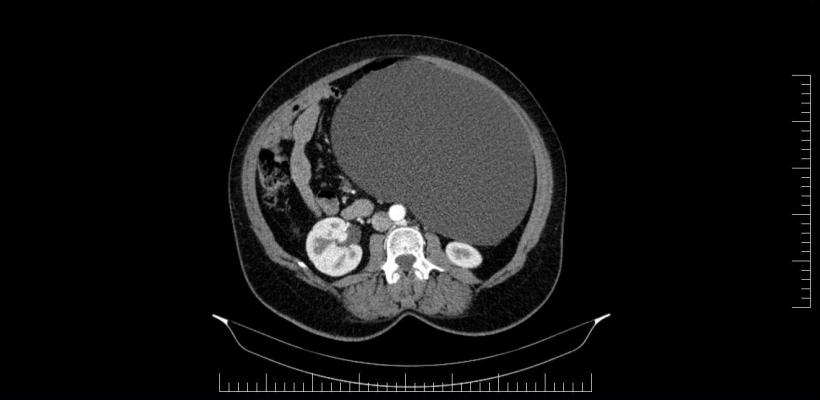

Performanță medicală la Sibiu: Chist ovarian de 4,5 kilograme, extirpat cu succes de la o pacientă | Galerie Foto | Imagine 3

Spitalul Militar de Urgență „Dr. Alexandru Augustin” Sibiu